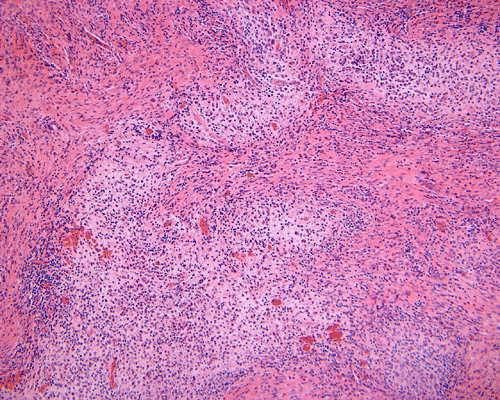

Clinical information: The patient was a 13 year-old girl who presented with worsening headache and some difficulties with memory, concentration and attention. MRI studies disclosed a 2.1 x 1.9 x 1.8 cm enhancing mass in the left temporal bone and sphenoid wing. The mass extended intracranially and abuts the left temporal bone accompanied by dural enhancement at that location. There is also extension through the bone into the submuscular temporal region. The following photos are taken from representative regions of the lesion. Panel 1 and 2 are CT scans at soft tissue and bone density respectively. Panel 3 and 4 are T1 weighed images without and with contrast respectively. Pandl 5 is proton density image. Panel A to D are cytologic (squash) prepartion for intra-operative consultation. Panel E and F are frozen sections for intraoperative consultation. Panel G to L are paraffin embedded sections.

Morphologic features are often sufficient to make an accurate diagnosis. Typical lesions are composed of medium sized to large Langerhans’ cells mixed with non-neopalstic inflammatory cells. The amount of eosinophils can vary from none 3 or scant to substantial. The Langerhans’ cells have only slight degree of atypia. Many of the nuclei have a characteristic deep groove parallel to the long axis, the so-called “coffee bean” nuclei. The amount of cytoplasm is usually moderate. Histiocytes (macrophages) are usually present and can be multinucleated. When histiocytes are present in large amount, they may make the diagnosis difficult. Similar to their non-neoplastic counterparts, tumor cells in Langerhans’ cell histiocytosis are positive for CD1a and S100 by immunohistochemistry. Histiocytes, on the other hands, are negative for S100 and CD1a 4, 5, 6 CD68 is helpful but not entirely specific in separating histiocytes from tumor cells in Langerhans’ cell histiocytosis. The proliferating fraction of can be recognized by immunohistochemistry for Ki67 (MIB-1) 6.